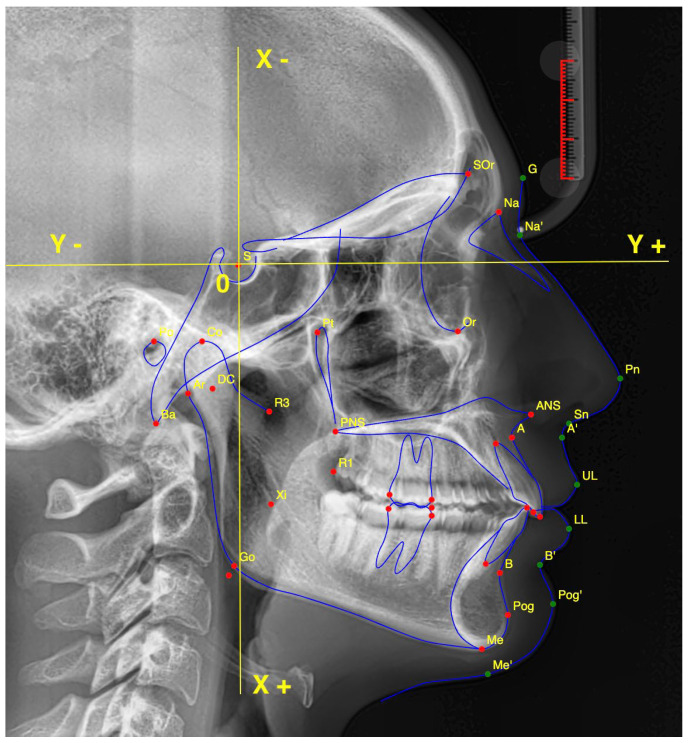

目的:本研究旨在评估人工智能(AI)识别头侧标志的可重复性,并将其与经验丰富的正畸医生手工追踪的性能进行比较。方法:选择一名符合严格入选标准的26岁女性患者的高质量侧位脑电图。使用WebCeph软件(版本1500)在三种实验设置中识别出18个头测地标:不修改图像的人工智能追踪(AInocut)、图像修改的人工智能追踪(AI-cut)和由正畸专家手动追踪。每个评估者在同一幅图像上重复该过程10次。记录X和Y坐标,并使用变异系数(CV)和质心距离分析评估再现性。统计学比较采用单因素方差分析和Bonferroni事后检验,显著性设置为p < 0.05。结果:AInocut重复性最高,平均CV值最低。这两种AI方法都比手动追踪显示出更高的一致性,特别是对于像Menton (Me)和Pogonion (Pog)这样的地标。Gonion (Go)在所有组中表现出最高的变异性。在鼻后棘(PNS)点上发现显著差异(p = 0.001),人工智能优于人工追踪。x轴的变异性一般高于y轴。结论:与经验丰富的操作人员手工追踪相比,人工智能在头测地标识别方面表现出更高的可重复性。虽然某些点表现出很高的一致性,但其他点——尤其是PNS和围棋——仍然具有挑战性。这些发现支持人工智能作为数字头测术的可靠辅助手段,尽管单张x线片的使用限制了其普遍性。需要更广泛的多图像研究来证实其临床适用性。

Objectives: This study aimed to evaluate the reproducibility of artificial intelligence (AI) in identifying cephalometric landmarks, comparing its performance with manual tracing by an experienced orthodontist. Methods: A high-quality lateral cephalogram of a 26-year-old female patient, meeting strict inclusion criteria, was selected. Eighteen cephalometric landmarks were identified using the WebCeph software (version 1500) in three experimental settings: AI tracing without image modification (AInocut), AI tracing with image modification (AI-cut), and manual tracing by an orthodontic expert. Each evaluator repeated the procedure 10 times on the same image. X and Y coordinates were recorded, and reproducibility was assessed using the coefficient of variation (CV) and centroid distance analysis. Statistical comparisons were performed using one-way ANOVA and Bonferroni post hoc tests, with significance set at p < 0.05. Results: AInocut achieved the highest reproducibility, showing the lowest mean CV values. Both AI methods demonstrated greater consistency than manual tracing, particularly for landmarks such as Menton (Me) and Pogonion (Pog). Gonion (Go) showed the highest variability across all groups. Significant differences were found for the Posterior Nasal Spine (PNS) point (p = 0.001), where AI outperformed manual tracing. Variability was generally higher along the X-axis than the Y-axis. Conclusions: AI demonstrated superior reproducibility in cephalometric landmark identification compared to manual tracing by an experienced operator. While certain points showed high consistency, others-particularly PNS and Go-remained challenging. These findings support AI as a reliable adjunct in digital cephalometry, although the use of a single radiograph limits generalizability. Broader, multi-image studies are needed to confirm clinical applicability.